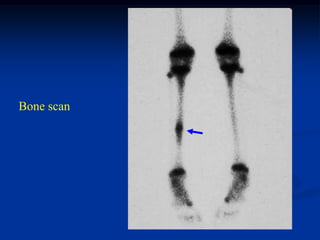

Bone scan